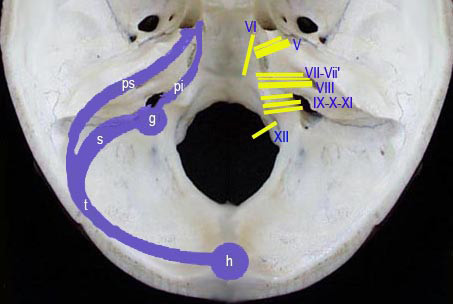

Les troncs nerveux issus du tronc crbral (pont & bulbe) sont tags de haut en bas :

V : les deux branches du Trijumeau

VI : nerf oculaire externe

VII & VIIÕ : nerfs Facial & Accessoire

VIII : nerf Auditif (acoustico-vestibulaire)

IX : Glossopharyngien

X : Pneumogastrique

XI : Spinal bulbaire

Sch.33

Les troncs nerveux en rapport avec lÕespace ponto-crbelleux sont issus des tages pontique & bulbaire du tronc crbral. Leur disposition spatiale est grossirement cardinale :

- en haut, le nerf trijumeau se dirige vers le ganglion de Gasser relais ganglionnaire de sa

racine sensitive ;

- en bas, les trois nerfs mixtes (IX, X, XI) orients vers le trou dchir postrieur ;

- plus en dedans, le VI ,

- en dehors, trois autres nerfs : le facial, le nerf de Wrisberg & le nerf acoustico-vestibulaire

orients vers foramen auditif interne. Ils constituent le principal constituant de cet espace.

Sch.34